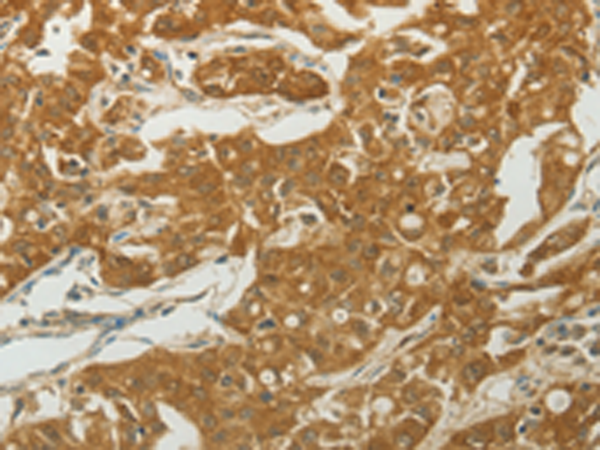

分类: 科研抗体货号: P11002别名: RYSR, BPIL1, LPLUNC2, C20orf184, dJ726C3.2应用: IHC反应种属: Human, Mouse